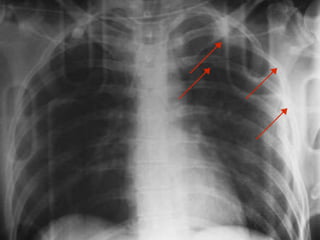

T E N S I O N

P N E U M O T H O R A X

• NOTE THE TRACHEAL

DEVIATION

• ABSENCE OF LUNG

MARKINGS LEFT

• DEEP SULCUS SIGN

LEFT

T E NS I O N P N E U M O T H O R A X • NOTE THE TRACHEAL DEVIATION • ABSENCE OF LUNG MARKINGS LEFT • DEEP SULCUS SIGN LEFT